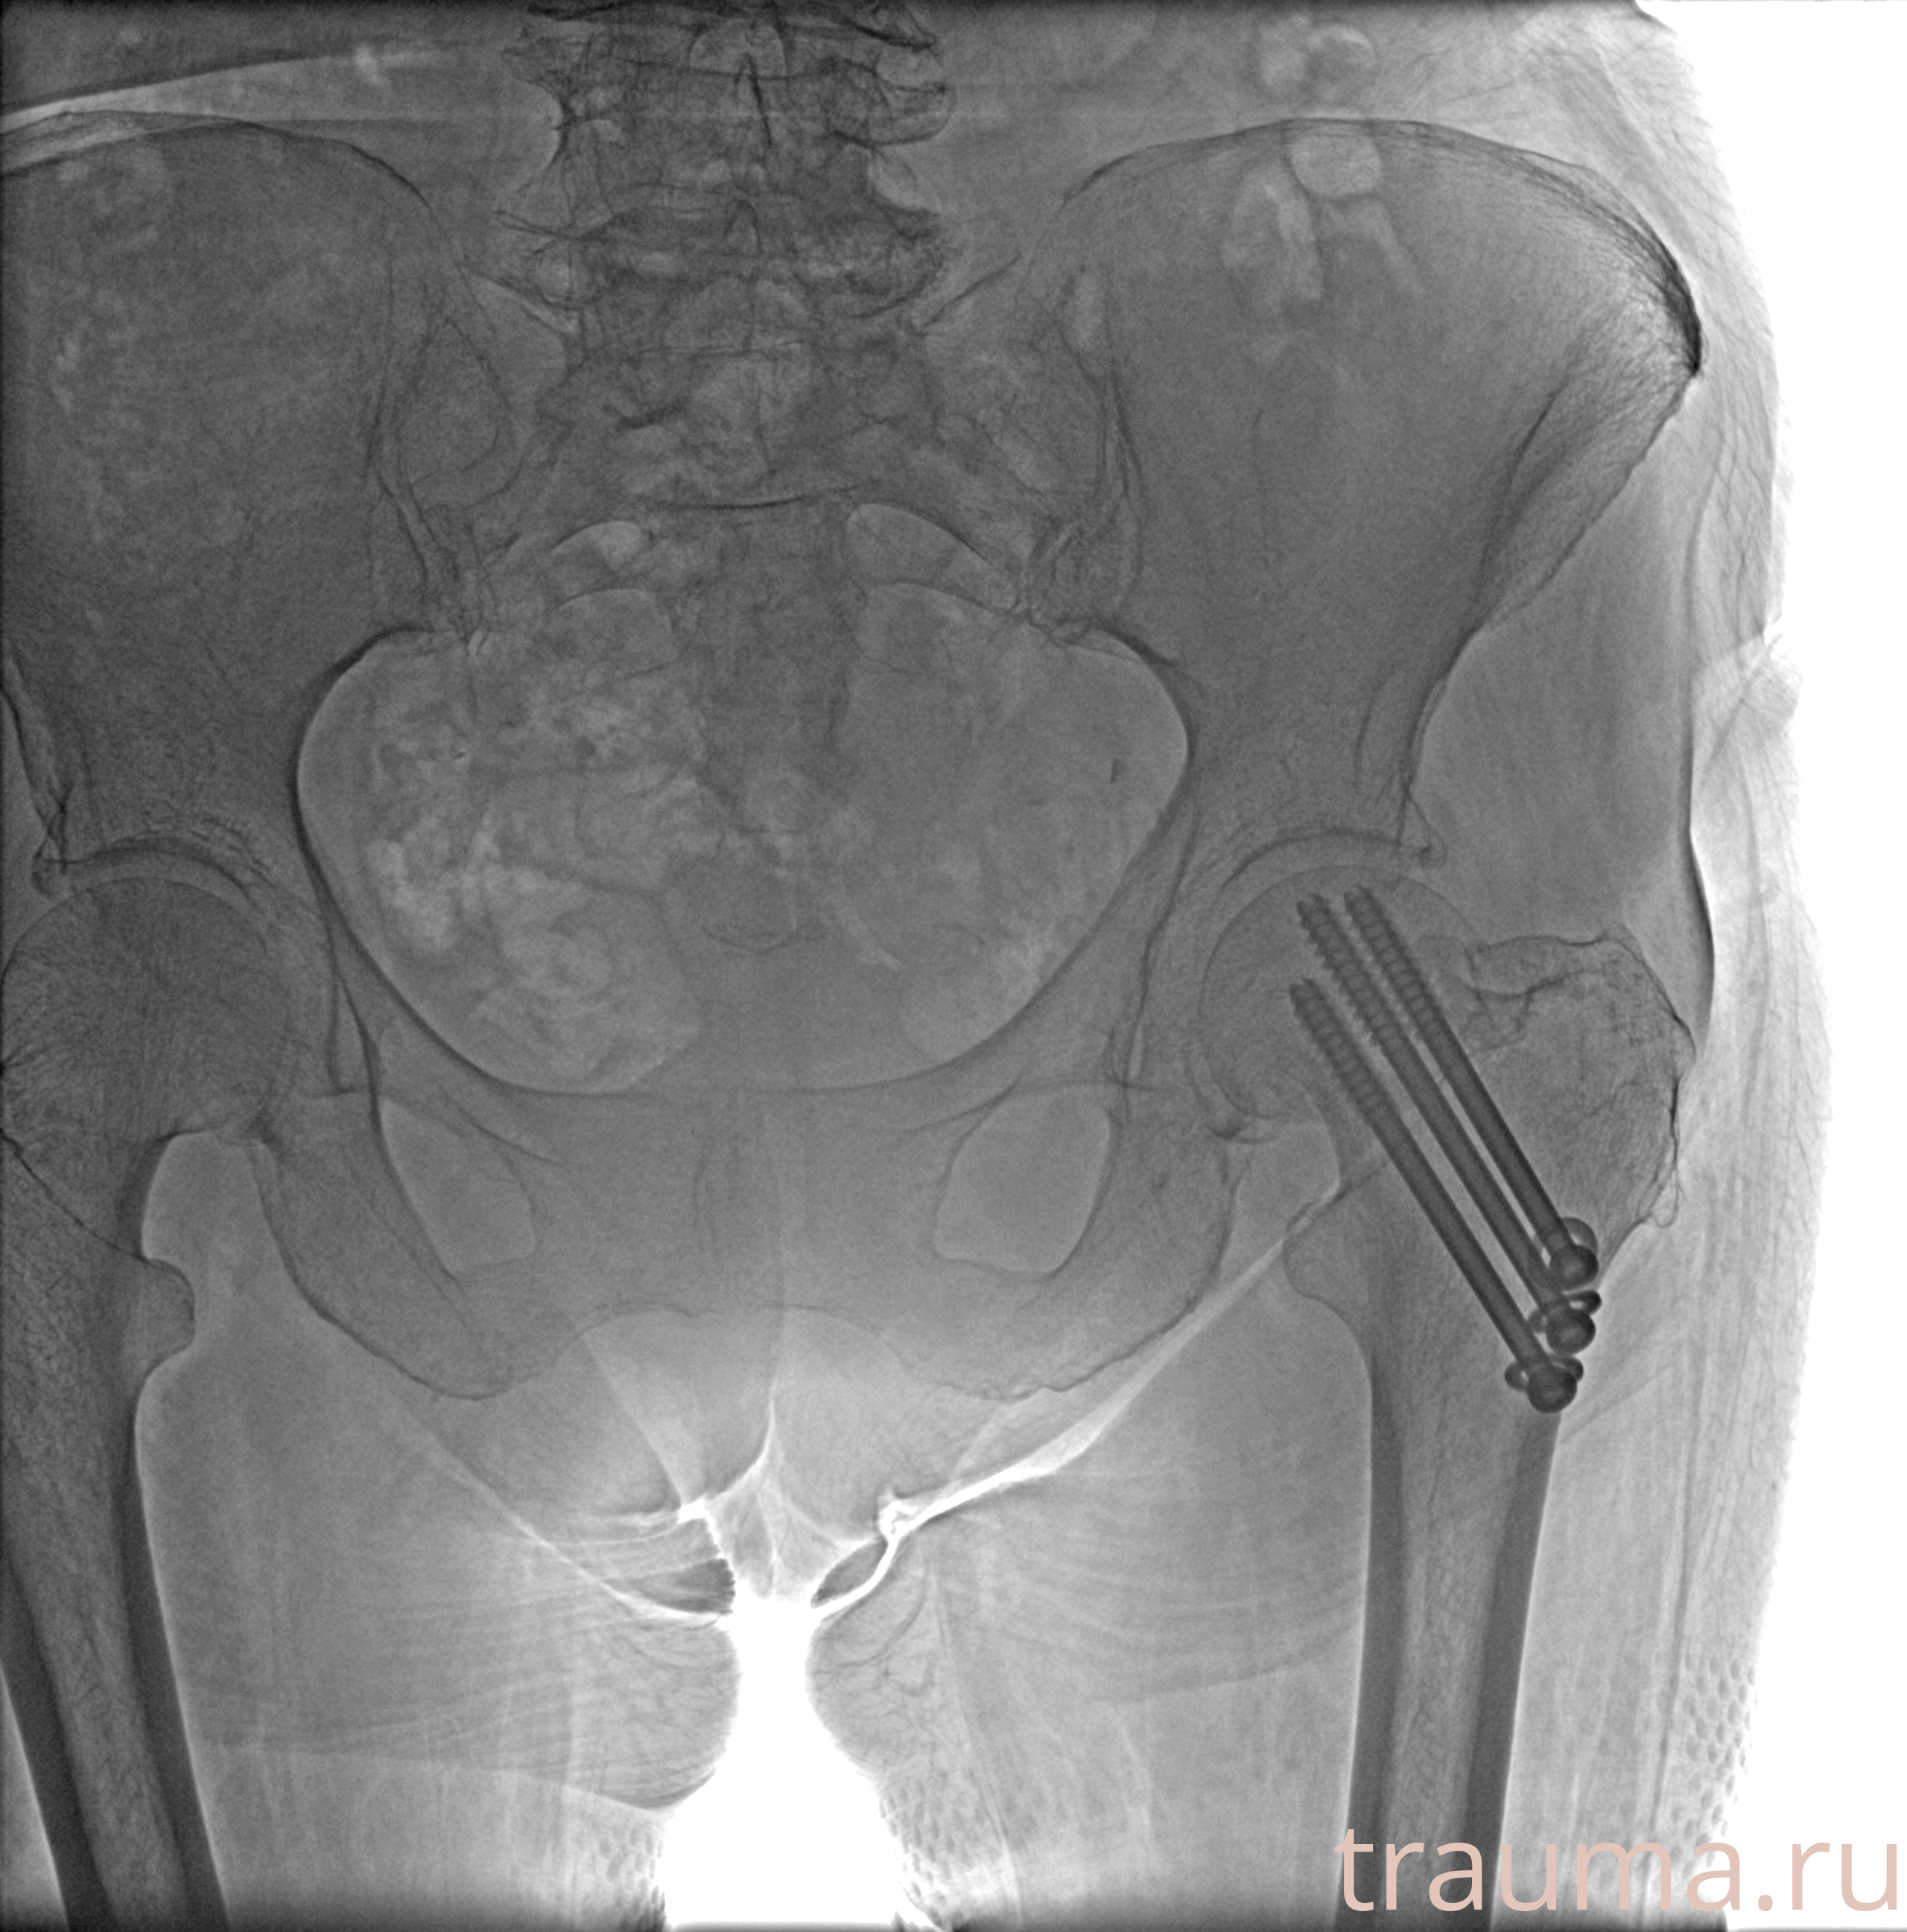

Рентгенограммы

Рентген на дому: по вашему адресу приезжает врач-рентгенолог, травматолог-ортопед с мобильным рентгеновским аппаратом, проводит диагностику травмы или заболевания, делает необходимые рентгенограммы, дает рекомендации по дальнейшему лечению. Получить качественные снимки в домашних условиях возможно благодаря уникальной методике, разработанной МосРентген Центром для института  Склифосовского